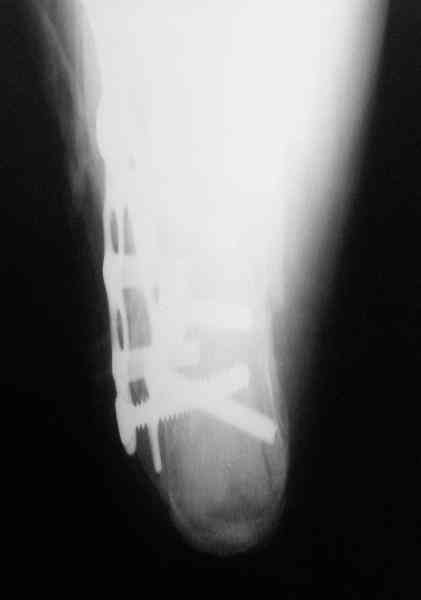

Пяточной пластиной

С уважением, А.Семенистый.

ГКБ № 13, Москва.

Открытый и закрытый способы лечения.